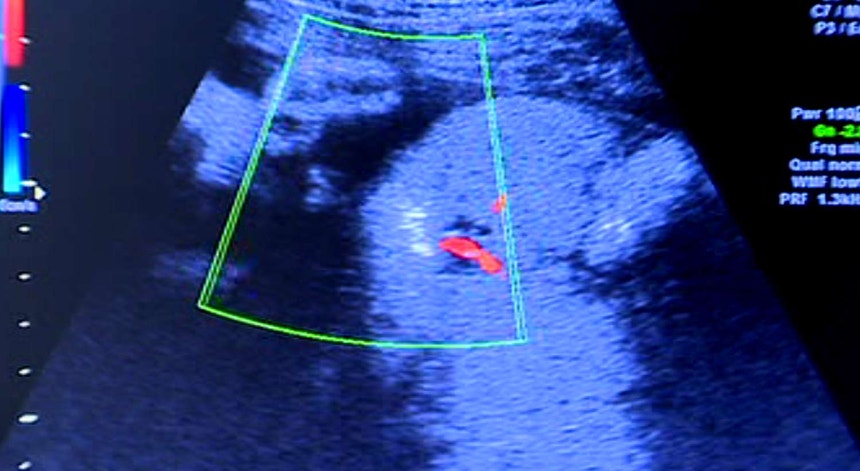

O Conselho Disciplinar Regional do Sul entendeu que, face à análise feita pelo relator dos vários processos pendentes, "existem fortes indícios de que as queixas poderão ter fundamento, sendo de realçar que não constam dos autos dos processos quaisquer respostas do arguido que possam contrariar tal convicção". Este órgão reuniu na terça-feira na sequência de uma solicitação do bastonário da Ordem dos Médicos, Miguel Guimarães, face à gravidade das acusações contra o referido médico que, nas ecografias realizadas numa clínica de Setúbal, não detetou malformações graves no rosto e no crânio de um bebé que nasceu dia 07 de outubro no Hospital São Bernardo, em Setúbal.